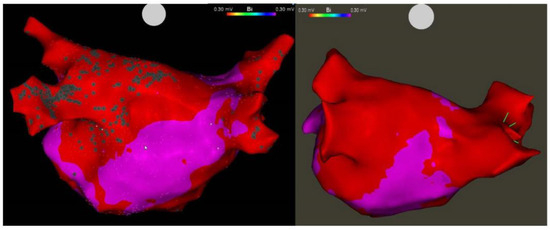

3.2. VoM Ethanol Infusion

- Pambrun, T.; Denis, A.; Duchateau, J.; Sacher, F.; Hocini, M.; Jaïs, P.; Haïssaguerre, M.; Derval, N. MARSHALL bundles elimination, Pulmonary veins isolation and Lines completion for ANatomical ablation of persistent atrial fibrillation: MARSHALL-PLAN case series. J. Cardiovasc. Electrophysiol. 2019, 30, 7–15. [Google Scholar] [CrossRef] [PubMed]

- Derval, N.; Duchateau, J.; Denis, A.; Ramirez, F.D.; Mahida, S.; André, C.; Krisai, P.; Nakatani, Y.; Kitamura, T.; Takigawa, M.; et al. Marshall bundle elimination, Pulmonary vein isolation, and Line completion for ANatomical ablation of persistent atrial fibrillation (Marshall-PLAN): Prospective, single-center study. Heart Rhythm 2021, 18, 529–537. [Google Scholar] [CrossRef]

- Lai, Y.; Liu, X.; Sang, C.; Long, D.; Li, M.; Ge, W.; Liu, X.; Lu, Z.; Guo, Q.; Jiang, C.; et al. Effectiveness of Ethanol Infusion into the Vein of Marshall Combined with a Fixed Anatomical Ablation Strategy (the “Upgraded 2C3L” Approach) for Catheter Ablation of Persistent Atrial Fibrillation. J. Cardiovasc. Electrophysiol. 2021, 32, 1849–1856. [Google Scholar] [CrossRef]